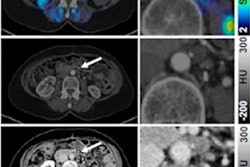

Ga-68 FAPI-PET/CT imaging in a 55-year-old male patient. No increased pulmonary tracer uptake was found (A, C). Tracer uptake colocalized with a sharply circumscribed, inhomogeneously contrast-enhancing mass on MRI without relevant diffusion restriction (B). Pathologic assessment diagnosed a tenosynovial giant cell tumor (D). Image courtesy of the Journal of Nuclear Medicine.Fibroblast activation protein (FAP) is overexpressed by cancer cells, and researchers suspect it is an essential component driving the growth of tumors. Experimental FAP-targeted molecular imaging radiotracers, such as FAPI-04 and FAPI-46, have shown promise in cancer research as well as for visualizing myocardial fibrosis.

Sellmann's team reported the rare tumor finding in a 55-year-old patient who underwent imaging due to persistent pulmonary symptoms after recovery from COVID-19. The patient was enrolled in a first-in-human trial testing Ga-68 FAPI-04 PET/CT scans (Biograph mCT, Siemens Healthineers) for identifying disease progression in 21 patients with interstitial lung disease.

The trial showed no increase in pulmonary radiotracer, but the researchers observed focally increased Ga-68 FAPI uptake in a mass in the patient's left thigh. Surgeons performed complete resection of the tumor.